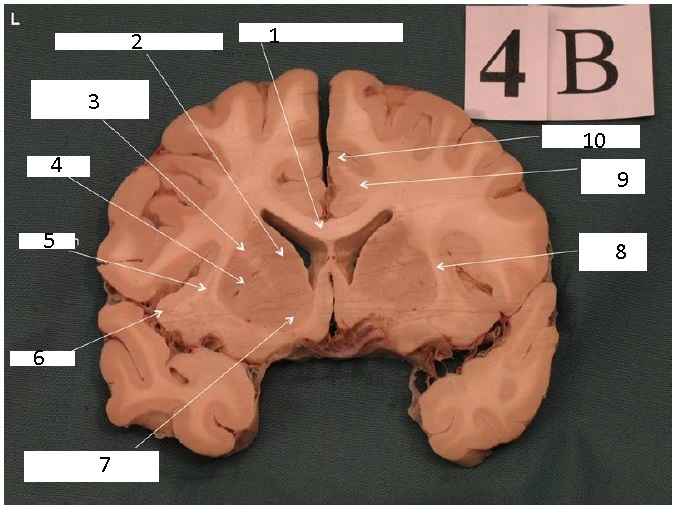

Identify 1

Body of Corpus Callosum

Identify 2

Caudate Nucleus

Identify 3

Anterior Limb of Internal Capsule

Identify 4

Putamen

Identify 5 and 6

5: Optic N

6: Optic Chiasm